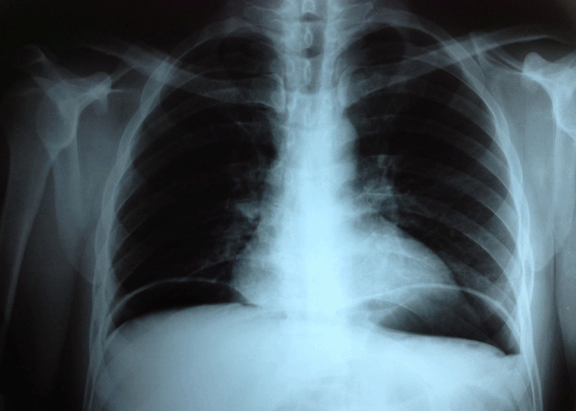

A 46-year-old male with history of chronic intermittent diarrhea and chronic lower-back pain was presented to our clinic with sudden diffuse abdominal pain irradiated to both shoulders. He had been on nonsteroidal anti-inflammatory drugs (NSAIDs) and prednisone (5–20 mg POq24h) for three years with partial back pain relief. Physical examination revealed diffuse tenderness and rigid abdomen with no bowel sounds. X-ray of chest showed a pneumoperitoneum. (Figure 1) A diagnosis of a possible peptic ulcer perforation was made. He was immediately managed with intravenous volume, nasogastric tube, intravenous proton-pump inhibitor (PPI), broad-spectrum antibiotics, and urgent laparotomy. During surgery a 3–4 mm perforation 50 cm before the ileocecal valve was found along with multiple focal mucosal ulcerations. (Figure 2) Partial bowel resection with an ileostomy was made. Erythrocyte sedimentation rate and C-reactive protein were elevated and a macrocytic anemia with low levels of serum B12 was documented. The ileum biopsy revealed focal ulcerations across the ileum wall with acute/chronic inflammation and no sign of malignancy. Ziehl-Neelsen and culture for tuberculosis were negative. Colonoscopy revealed focal ulcerations and pseudopolyps adjacent to areas of normal appearing mucosa with the characteristic cobblestone appearance and the same pathologic findings of the previous ileum biopsy. The compatible clinical history along with the laboratory, endoscopic and pathology findings made the final diagnosis of Crohn’s disease. Treatment with azathioprine and mesalamine was initiated. The patient had an uneventful recovery and at a six-month follow-up he was asymptomatic. An unexpected diagnosis of Crohn’s disease was made, probably partially masked over the last three years by the chronic glucocorticoid therapy used for the chronic lower-back pain that was finally attributed to a spinal disc hernia. Human Leukocyte Antigen (HLA)-B27 was negative and there was no sign of spondylitis or sacroiliitis.

Figure 1: Chest X-ray showing air under both diaphragms confirming the presence of pneumoperitoneum.